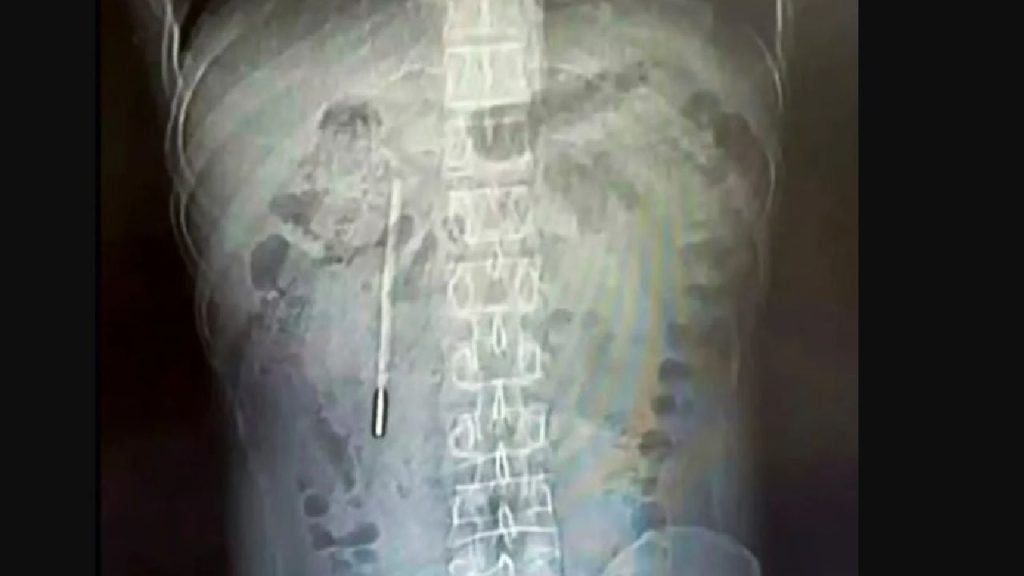

Un bărbat din China a descoperit, după două decenii de dureri abdominale, că disconfortul era cauzat de un termometru cu mercur înghițit accidental în copilărie. Wang, în vârstă de 32 de ani, a trecut printr-o intervenție chirurgicală de urgență pentru a îndepărta obiectul străin, descoperirea stârnind uimire în rândul medicilor și al publicului.

Incidentul, petrecut acum 20 de ani, a rămas uitat până când durerile abdominale persistente l-au determinat pe Wang să caute ajutor medical. Examinările medicale au relevat prezența termometrului în duoden, o parte a intestinului subțire. Situația era cu atât mai periculoasă cu cât termometrul era poziționat foarte aproape de peretele intestinal, crescând riscul de perforație și hemoragie.

Wang a recunoscut că a înghițit termometrul la vârsta de 12 ani. Din teama de a-și supăra părinții, nu a dezvăluit niciodată incidentul, iar lipsa simptomelor pe parcursul anilor a dus la uitarea evenimentului. Medicii au reușit să extragă termometrul intact, chiar dacă marcajele de pe acesta se șterseseră complet, după cum au precizat la finalul intervenției.